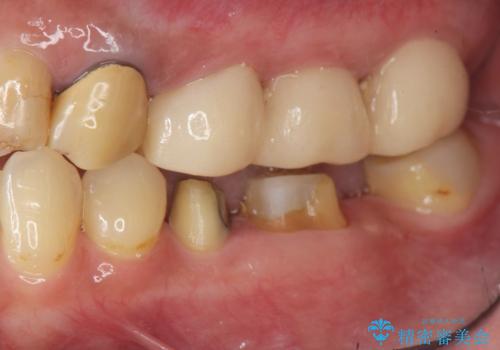

- 他院で根の治療まで終え、違和感が取れず相談に来院されました。

当該歯を精査したところ、歯根に破折が見られ抜歯を余儀なくされました。